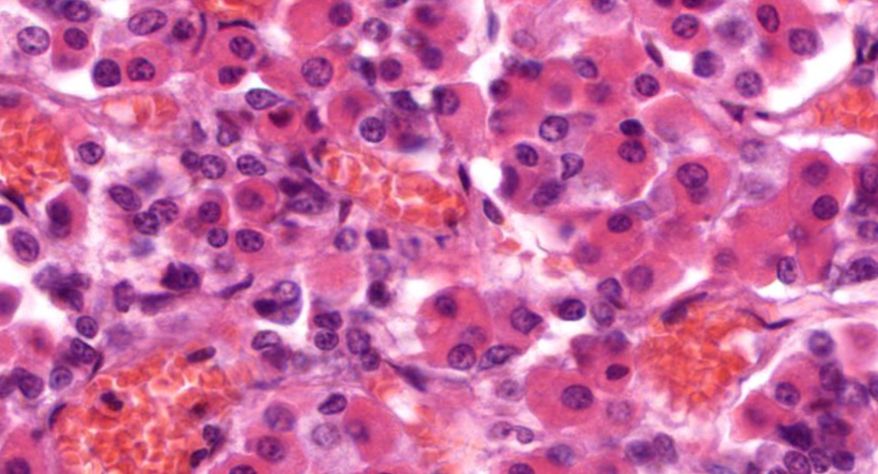

低倍镜观察:1. 被膜:由薄层结缔组织组成。2. 实质:由许多大小不等的滤泡构成。滤泡壁是单层立方上皮细胞,滤泡腔内充满粉红色匀质胶状物,滤泡之间的结缔组织内有丰富的血管。高倍镜观察:1. 滤泡:滤泡壁的单层滤泡上皮细胞一般呈低柱状或立方状,胞质着浅色,细胞核呈圆形。滤泡腔内充满了粉红色匀质胶质。2. 滤泡旁细胞:体积较大,呈圆形或椭圆形;细胞核较大,呈圆形,着色较浅,细胞质染色也较浅。细胞或嵌在滤泡壁上或成团分布于滤泡之间。3. 间质:由结缔组织组成。位于滤泡之间。其中含有丰富的毛细血管及三五成群的滤泡旁细胞。

3.滤泡上皮细胞

4.胶质

5.滤泡旁细胞1

7.滤泡旁细胞2